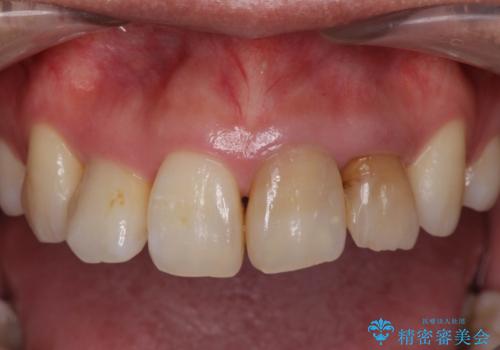

- 神経の死んでしまっている前歯の変色の改善を求めて来院されました。

根管治療をしたのち時間が経過して変色が目立つ歯と、レジン充填が複数箇所に及んでいる歯も同時にオールセラミック治療を行っていくこととなりました。